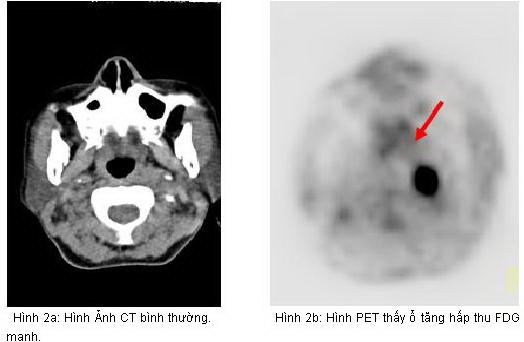

Hình 1: Hình ảnh PET tổng thể cho thấy các tổn thương tăng hấp thu

FDG bất thường tại các vị trí mũi tên

pet.jpg

Hình 2c: Hình PET/CT thấy tổn thưởng tăng hấp thu

FDG tại vùng vòng họng bên trái

Kết quả PET/CT: tổn thương tăng hấp thu FDG mạnh tại vòm họng bên trái, max SUV=11,8, các tổn thương di căn hạch tại vùng cổ bên phải và bên trái.

Trong khi đó kết quả nội soi vòm họng và CT không phát hiện thấy tổn thương u nguyên phát (CT-) bởi vì tổn thương ở mức độ chưa xâm lấn ra bề mặt niêm mạc vòm họng và mà mắt chưa thể nhận thấy được  qua  nội soi, CT...

Dựa vào các kết quả trên, bệnh nhân được chẩn đoán là ung thư vòm họng di căn hạch cổ hai bên. Đồng thời đánh giá được giai đoạn bệnh của bệnh nhân là T1N2M0, kế hoạch điều trị tiếp theo là xạ trị phối hợp hoá trị.